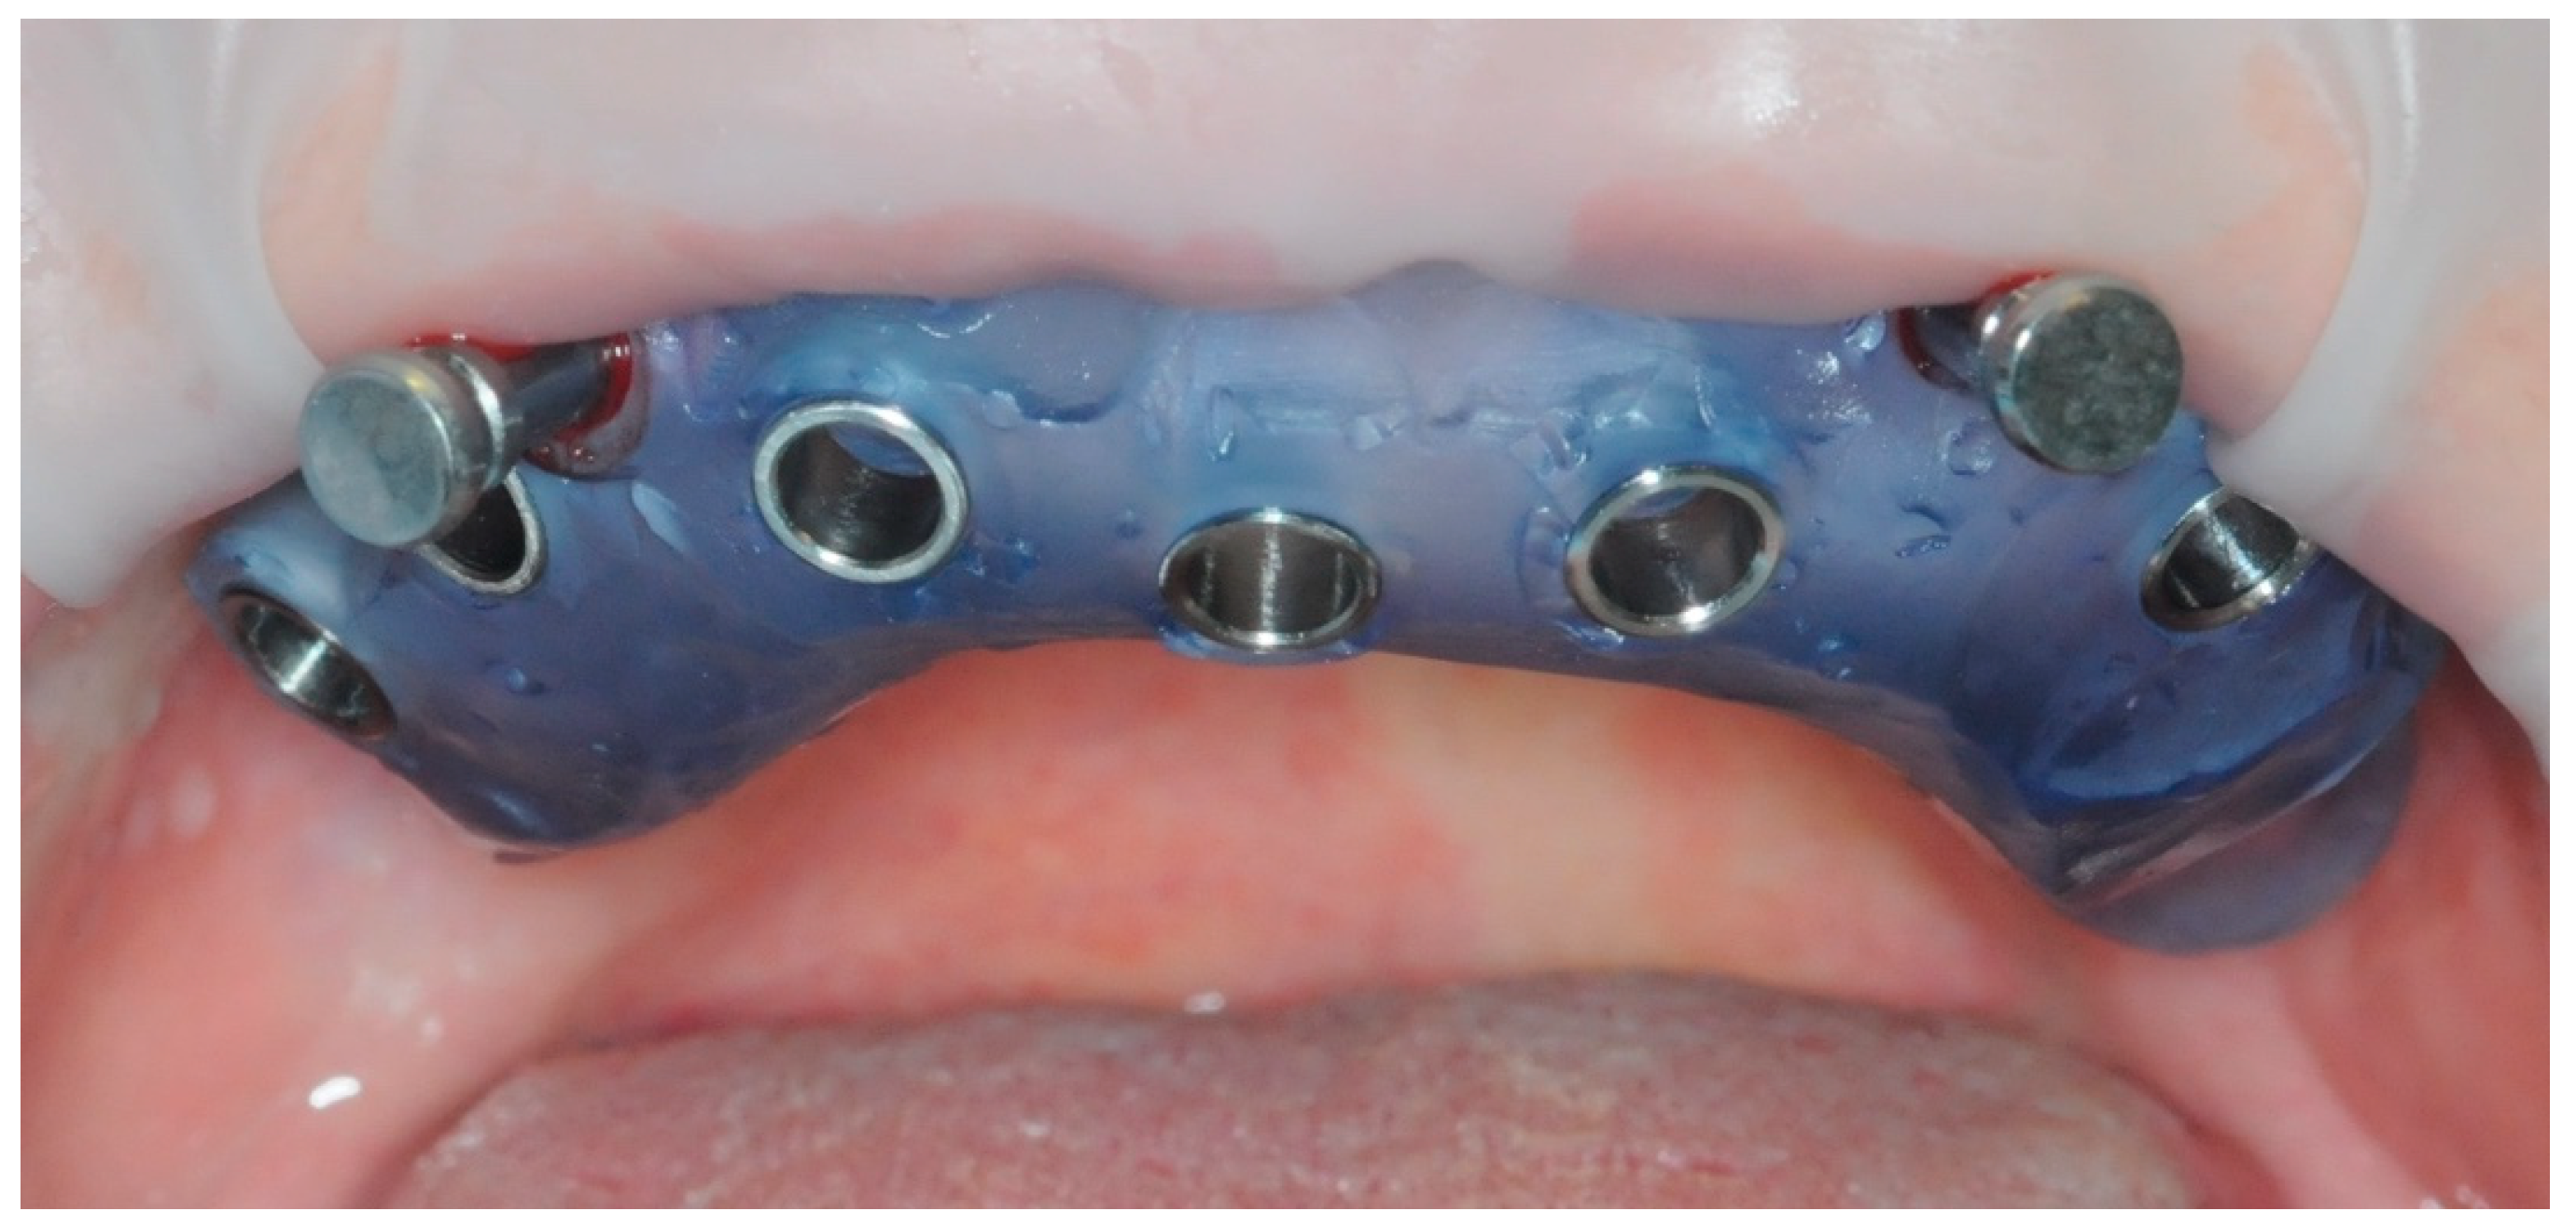

2.1. Surgical Guide Design

2.2. Surgery